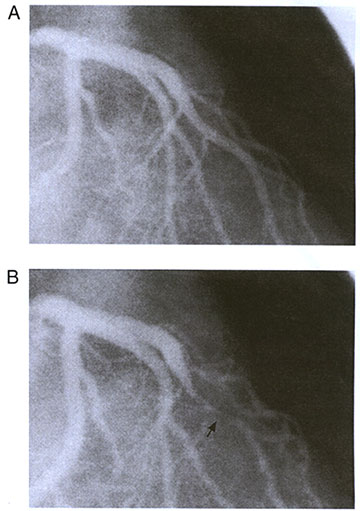

Figure 212-11

Coronary angiogram of a patient with myocardial bridging of the left anterior descending coronary artery in the right anterior oblique position. (A) An absence of constriction during diastole is shown. (B) This depicts the "milking effect" during systole (arrow).

Symptomatic Myocardial Bridges:An Overview.JACC,Vol. 41,No.3, Feb.5.2003, pp.351-359.